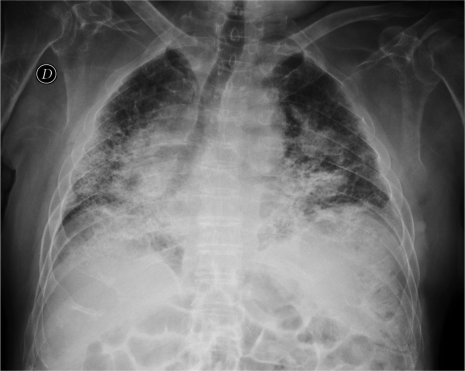

CASO: Paciente inmunodeprimido con Disnea.

Hallazgos:

- En la placa PA hay opacidad difusa bilateral de ambos hemitorax en vidrio deslustrado. En bases pueden intuirse opacidades mutifocales. La placa lateral también muestra la opacidad total del parénquima.

IMPORTANTE: Estos hallazgos son inespecíficos, pero ante un paciente inmunodeprimido, la evidencia de opacidad en forma de vidrio deslustrado, más aun si es de predominio perihiliar y en lóbulos superiores, hay que descartar en primer lugar una neumonía por Neumocistis, que en nuestro medio suele vincularse a pacientes VIH positivos.

VIDRIO DESLUSTRADO: Aumento de densidad difusa que no impiden la visualización de los vasos pulmonares que contienen. Se puede ver en afectación del espacio aéreo y/o del intersticio.

Causas:

- Infecciosas (P.Jiroveci y CMV)

- Neumonía intersticial descamativa.

- Alveolitis alérgica extrínseca.

- Sarcoidosis.

- Neumonía intersticial habitual.

- Proteinosis alveolar.

- Neumonía organizada criptogénica